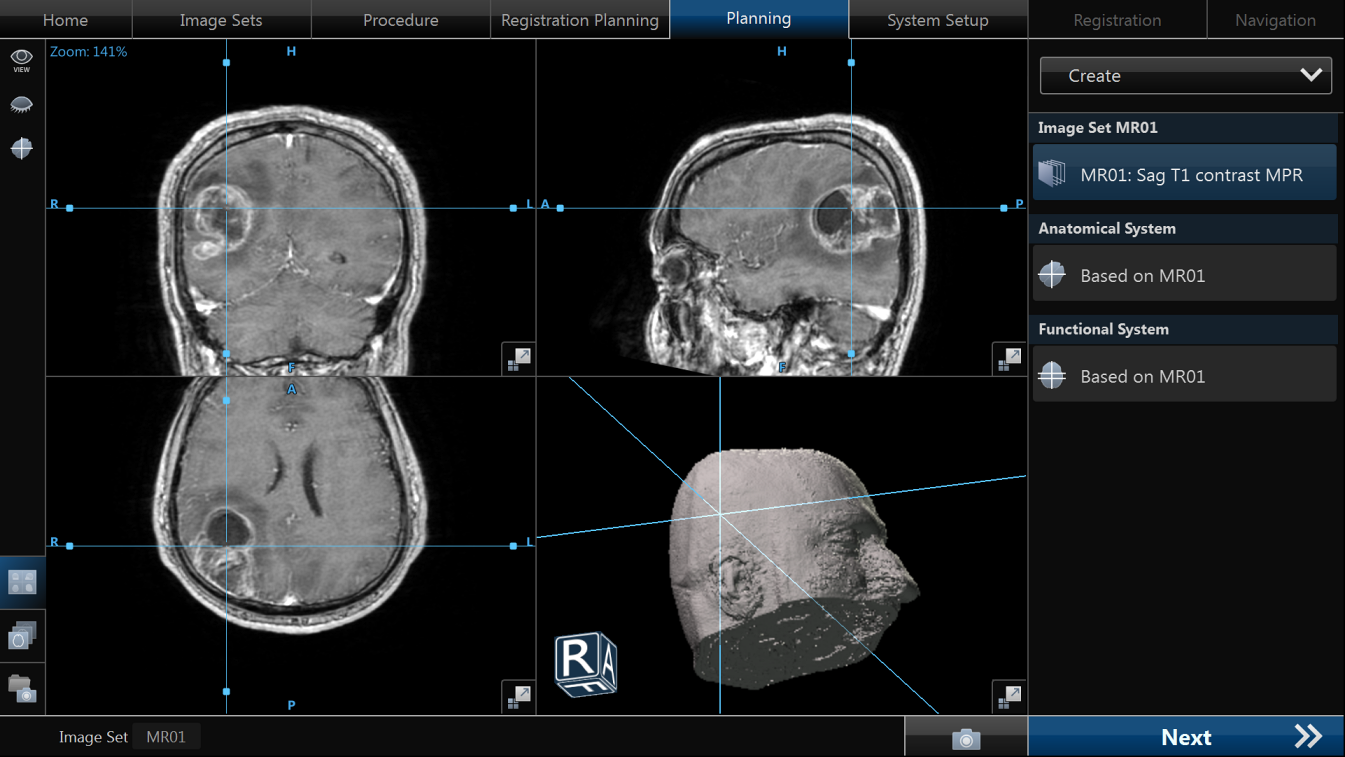

- neuronavigația oferă orientare spațială precisă

- Obligatoriu RMN cerebral cu contrast și protocol 3D pentru neuronavigație.

- Mijloace: microscop operator, neuronavigație, monitorizare neurofiziologică intraoperatorie (awake surgery), fluorescență 5-ALA.